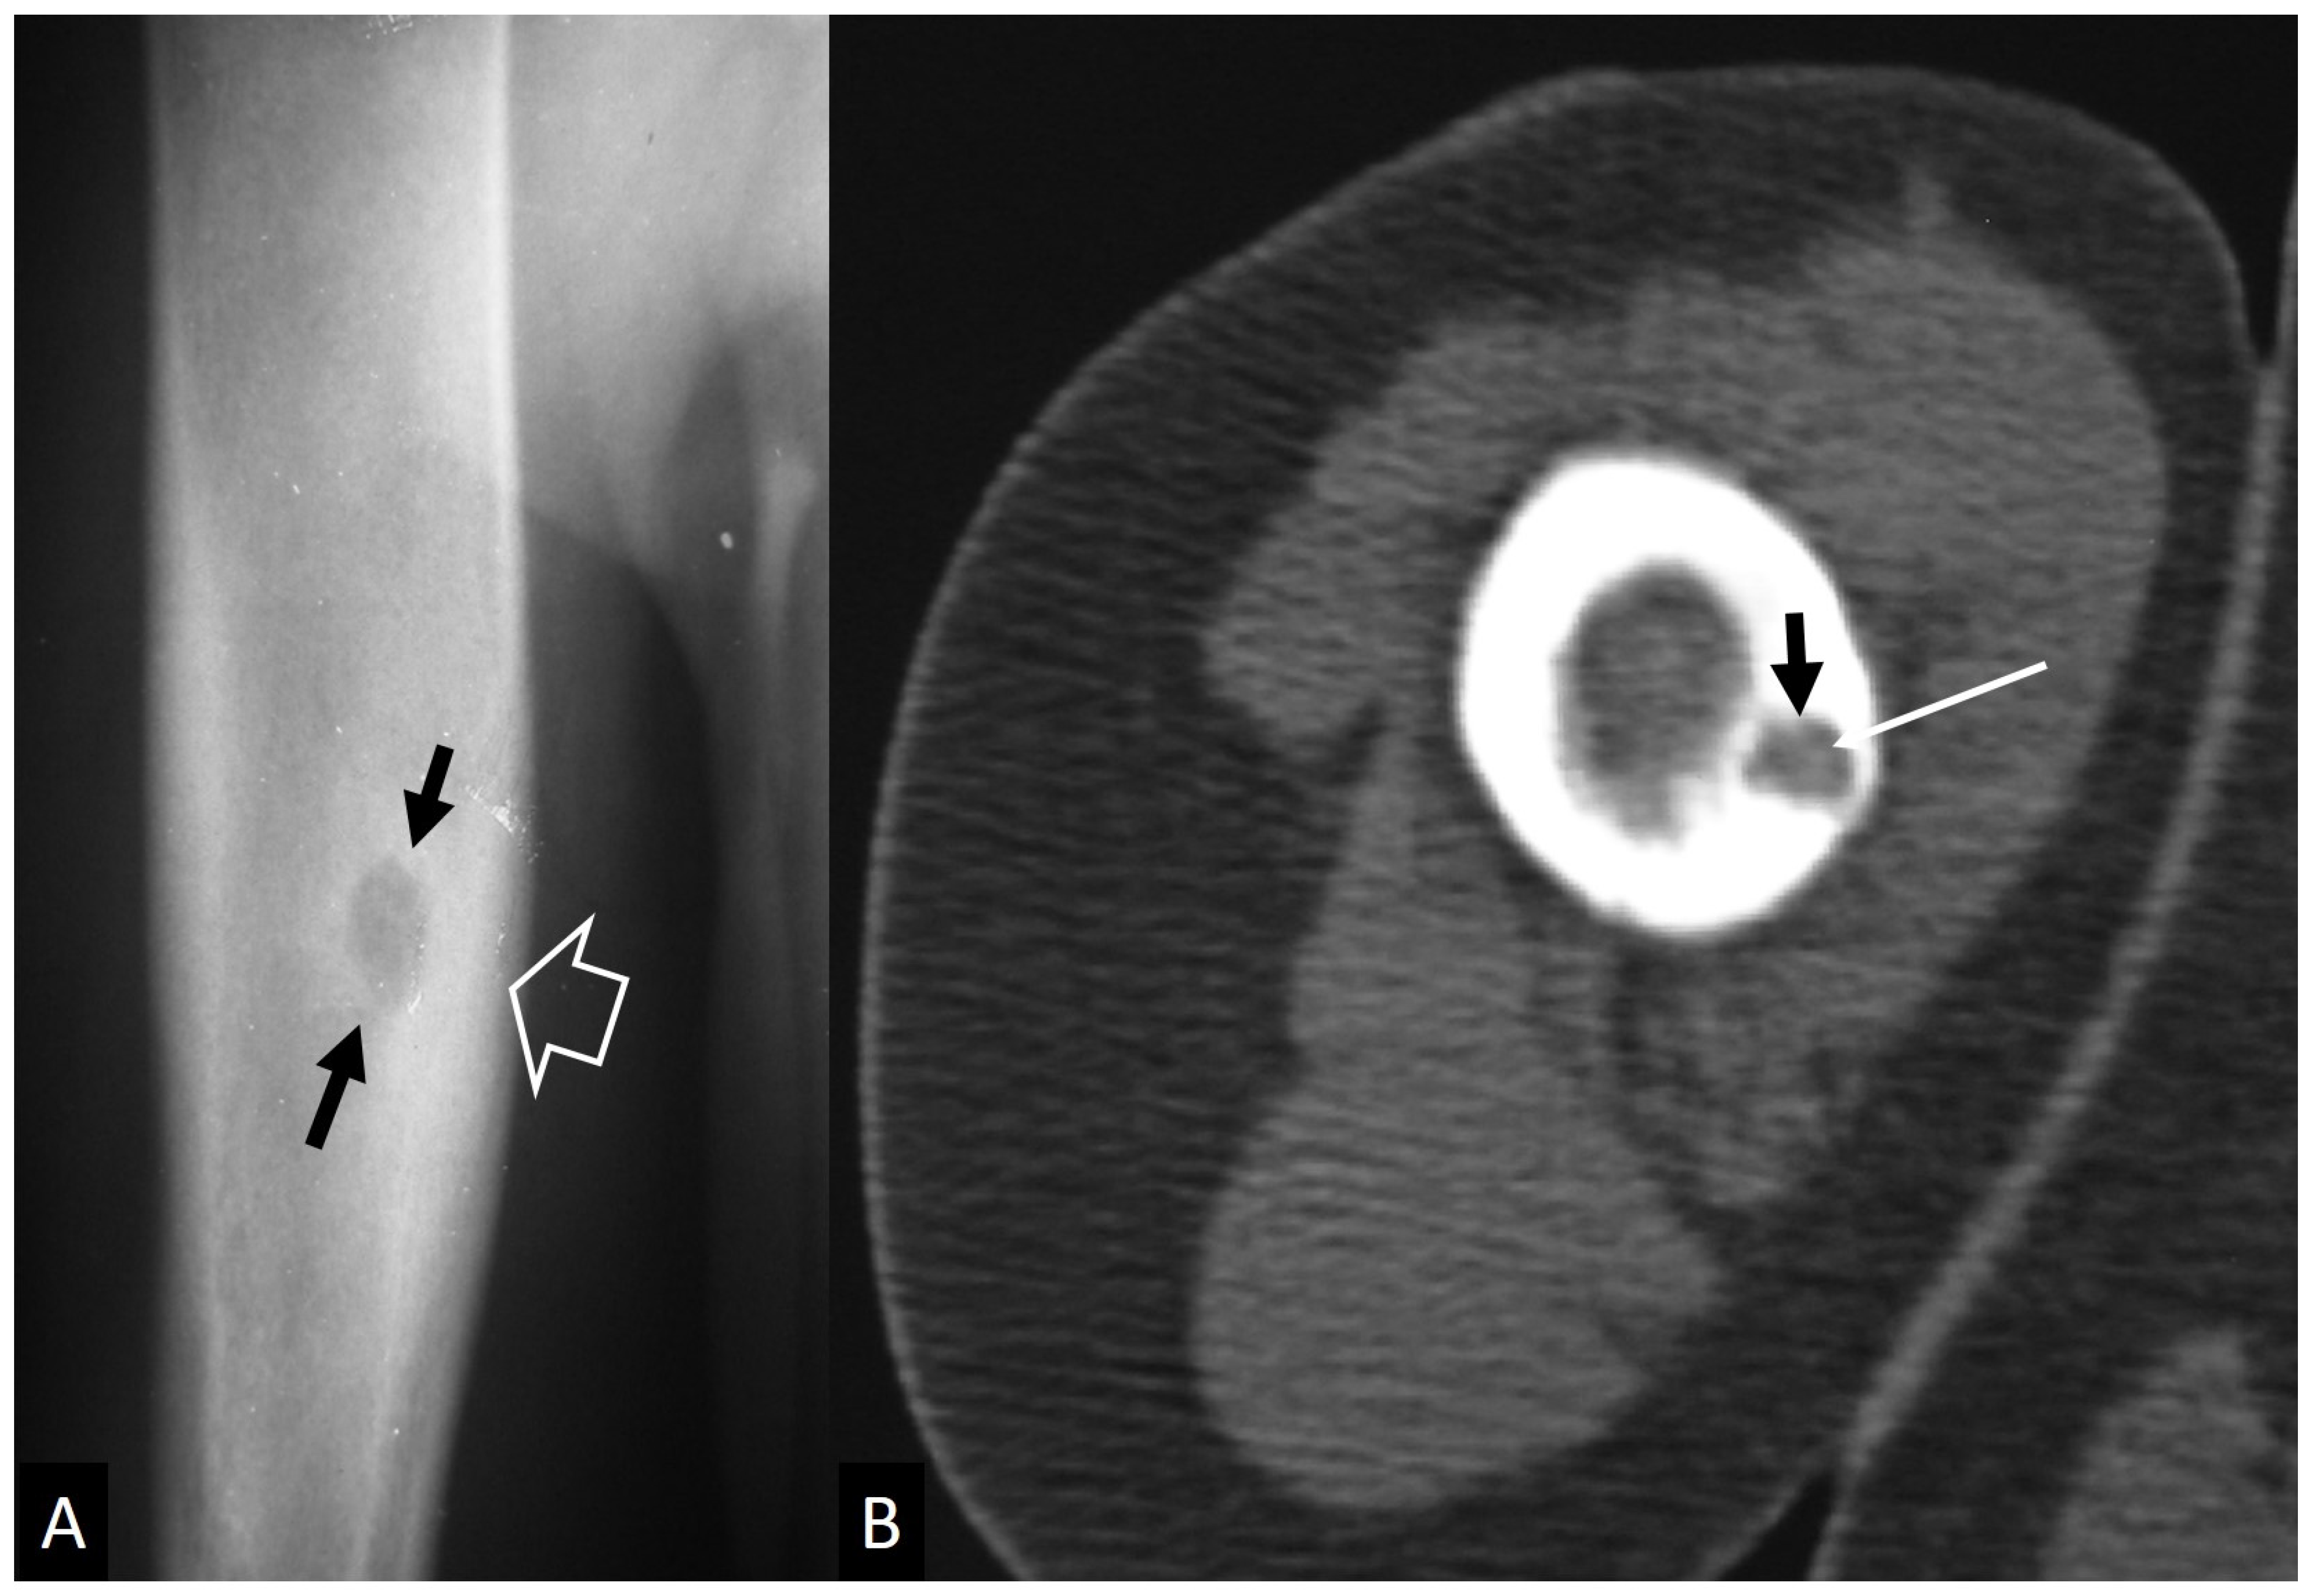

3.2.1. Ewing’s Sarcoma

3.2.2. Lymphoma